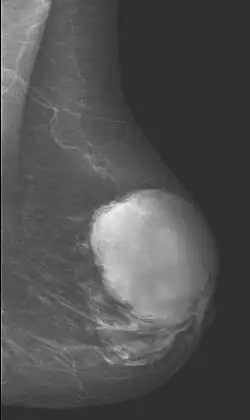

Das Cystosarcoma phylloides (synonym Phylloidtumor), auch Zystosarkom (der Brust) genannt, ist ein seltener Tumor an der Brust (Mamma) der erwachsenen Frau. Er hat Anteil von ca. 1 % an allen Brustdrüsentumoren.

Der Tumor zeigt sich als finger- oder keulenartige Wucherung des Bindegewebes und der Brustdrüse. Er wird als Sonderform des Fibroadenoms (gutartige Geschwülste der weiblichen Brust) angesehen. Phylloidtumore sind aber oft größer als diese und wachsen mit fingerartigen Ausläufern in das umgebende Brustgewebe. Der Tumor wächst (meist schnell) in Schüben und kann zu erheblicher Brustdeformation führen und auch die ganze Brust befallen.

Die Knoten des Tumors sind meist gut zu ertasten. Die Oberfläche ist sehr unregelmäßig. Der Tumor kann durch die Haut „blumenkohlartig“ nach außen gelangen. Da der Tumor sehr schnell wächst, kann er zu einer erheblichen Brustvergrößerung führen.

Zur Abgrenzung zum Fibroadenom reichen Mammographie und Sonographie nicht aus. Erst andere bildgebende Verfahren wie MRT und eine Gewebeprobe (Biopsie) ermöglichen die sichere Diagnose. Die Klassifikation der Bösartigkeit basiert auf dem Anteil der entarteten Zellen.